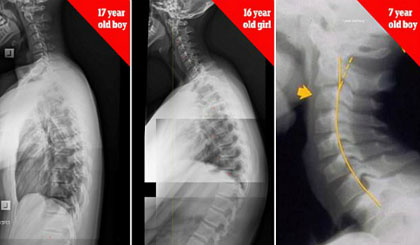

Xương sống của bé trai 17 tuổi, bé gái 16 tuổi và bé trai 7 tuổi bị biến dạng do nghiện thiết bị điện tử. Ảnh: James Carter.

Nhiều phụ huynh khi thấy con em dùng điện thoại chỉ quan tâm liệu trẻ có xem các nội dung không phù hợp mà không nhắc nhở về tư thế ngồi. Chuyên gia trị liệu cột sống là tiến sĩ James Carter (Australia) cảnh báo trẻ em 7 tuổi có thể bị gù lưng, cong vẹo cột sống do sử dụng smartphone và tablet quá nhiều. Hội chứng được gọi là "chiếc cổ nhắn tin" đang gia tăng một cách đáng báo động.